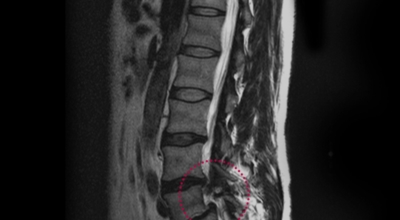

경추 사이의 추간판(디스크)이 탈출 또는 파열되어 경추신경이 자극이나 압박을 받아 통증이 생기는 증상을 말해요. 경추는 운동성이 큰 부위로 추간판이 압력을 받으면 튀어나와 척수나 신경을 압박하게 되는데요 목디스크는 퇴행성 변화 이후에 발생되기 때문에 많은 환자들이 만성적인 통증을 지니고 있는 경우가 많아요. 급성으로 생기는 경우는 교통사고, 추락, 스포츠 활동에 의한 목 부상으로 나타나기도 해요. 20대부터 가벼운 초기 증상으로 시작하여 옳지 않은 습관으로 악화되거나 호전되기를 반복해요. 나이가 들면 퇴행성 변화로 40~50대에 가장 많은 환자 수를 보인다고 합니다

비수술적 치료가 효과가 없다거나 디스크의 신경압박이 정도가 심한 경우엔 시술할 관조차 들어갈 공간이 없으니 비수술을 고집하는 경우 주변의 정상조직까지 훼손이 될 위험이 있답니다. 미세 현미경 수술이나 인공 디스크 치환술 및 경추유합술을 통해서 치료가 가능한데 가급적 비수술치료가 권장되지만 정확한 진단이 먼저되어야 하기 때문에 자세한 사항은 전문의와 상담해서 결정하는 것이 좋을겁니다.

신경성형술은 목디스크 치료방법 중 비수술치료로 1mm의 초소형 카테터를 삽입하여 통증의 원인의 부위를 찾아서 신경의 유착을 풀어 주는 시술입니다. 가장 대중적으로 활용되고 있는 척추질환 비수술치료로서 신경성형술의 장점은 크게 5가지로 볼 수 있어요. 20분 이내의 짧은 시술이므로 수술에 대한 부담이 적습니다. 또 입원을 하지 않고 시술 후 일상생활이 바로 할 수 있는 것이 장점이예요.